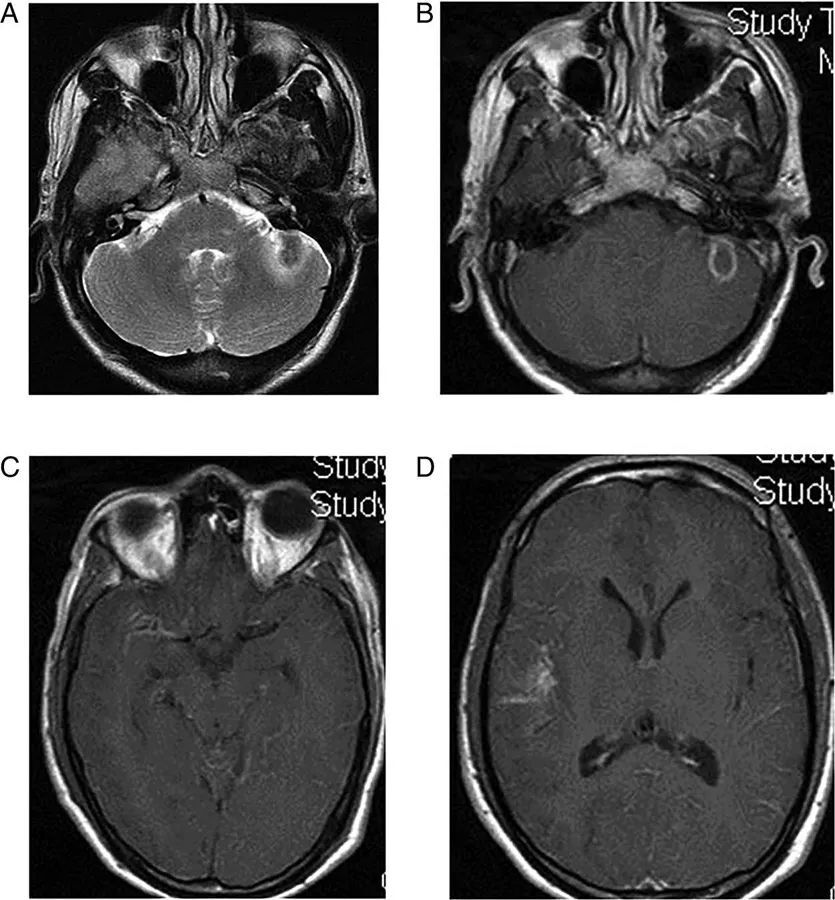

图13  软骨肉瘤。可见肿物破坏颅底,以左内耳骨裂缝为中心,延伸至桥小脑角和海绵窦。其发源位置和T2W上的明亮信号表明它是一种软骨瘤,颅底的CT扫描骨窗证实了病灶的起源和骨质破坏的性质

图14  脊索瘤。中线区可见一巨大不规则占位,斜坡和蝶窦被破坏,肿瘤延伸到右侧的脑池和桥小脑角区。脊索瘤在MRI上通常表现为T2高信号和T1上的局灶性高信号

图15  多发副神经节瘤。患者右侧有搏动性耳鸣,影像学可见右侧颈静脉球瘤以颈静脉为中心延伸到右侧桥小脑角,由血管流空信号和出血性变化组合而产生典型“胡椒盐”外观